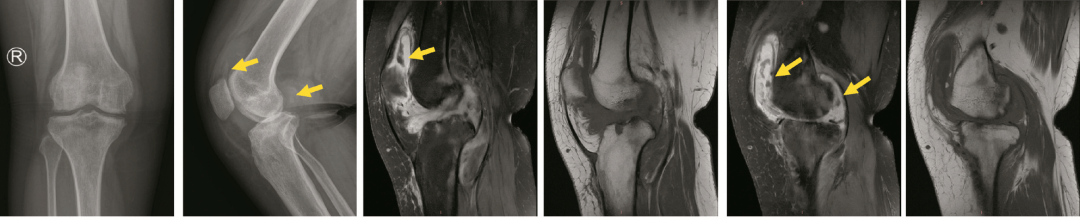

图1 术前的影像学资料

右膝关节影像学评估显示典型特征:前后位(A)和侧位(B)X线片均可见关节旁骨质疏松、多发骨侵蚀及关节内游离体(箭头所示)。后续磁共振成像(MRI)检查中,脂肪抑制T2加权序列(C、E)和T1加权序列(D、F)均显示关节内存在多发游离体(箭头所示)。